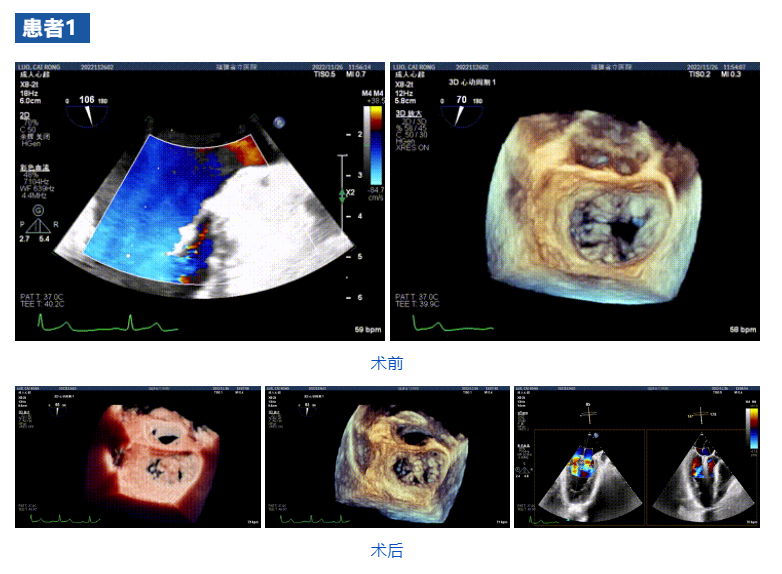

接受治療的三例患者均為器質(zhì)性重度二尖瓣反流(DMR)患者,術(shù)前超聲提示二尖瓣后葉脫垂伴4+反流,左室舒張功能減退。郭延松教授攜同團(tuán)隊(duì)成員陳新敬副教授和洪景宣、方明程、楊清勇主治醫(yī)師、心外科丁杭主任以及超聲科賴(lài)寶春、葉振盛主治醫(yī)師共同進(jìn)行病情討論??紤]到患者高齡、基礎(chǔ)疾病多、STS評(píng)分高,為外科手術(shù)極高危患者,不適合進(jìn)行外科開(kāi)胸二尖瓣手術(shù),因此決定為患者實(shí)施經(jīng)導(dǎo)管緣對(duì)緣修復(fù)介入術(shù)(JensClip經(jīng)導(dǎo)管瓣膜夾系統(tǒng))。

在浙江大學(xué)醫(yī)學(xué)院附屬第二醫(yī)院王建安教授團(tuán)隊(duì)的支持下,手術(shù)經(jīng)股靜脈-房間隔入路,采用全身麻醉插管,在TEE和DSA引導(dǎo)下完成房間隔穿刺。置入JensClip瓣膜夾系統(tǒng)后,在左房調(diào)整瓣膜夾的位置和軸向,后進(jìn)入左室,在TEE引導(dǎo)下捕捉二尖瓣前后瓣葉,并關(guān)閉瓣膜夾。經(jīng)TEE反復(fù)確認(rèn)手術(shù)效果后最終鎖定并釋放瓣膜夾。術(shù)后即刻超聲顯示瓣膜夾位置穩(wěn)定,功能良好,二尖瓣反流由術(shù)前4+減少至微量,手術(shù)圓滿成功。